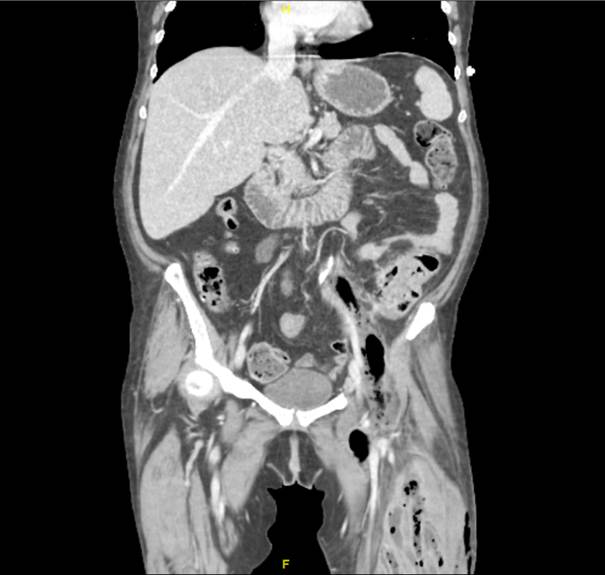

La TC mostraba una colección hidroaérea en psoas y retroperitoneal que asciende hasta la cavidad abdominal hallándose una diverticulitis perforada. El tratamiento quirúrgico se basó en el drenaje de la colección retroperitoneal y sigmoidectomía, seguido de una fasciotomía, desbridamiento y lavado del muslo.

La perforación de un divertículo puede formar un absceso intraperitoneal desarrollando una peritonitis o un absceso retroperitoneal, derivando en una translocación bacteriana hacia la extremidad inferior, debido a la comunicación existente en el anillo crural, generando una fascitis necrotizante del miembro.